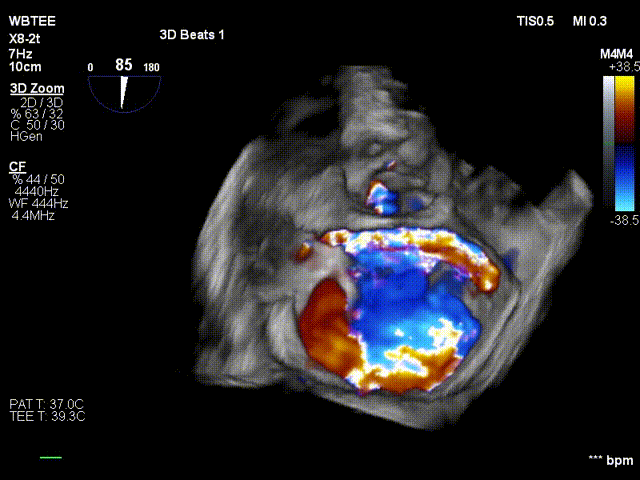

反复测试二尖瓣钳夹的稳定性,超声复查提示二尖瓣夹内侧反流有效改善,外侧仍有部分反流,平均跨瓣压差2mmHg,肺静脉收缩期逆流频谱恢复正向,傅国胜教授团队与超声影像团队充分沟通讨论,计划在二尖瓣夹外侧再置入第二枚二尖瓣夹,遂精准释放第一个二尖瓣夹。

傅国胜教授继续在食道超声影像引导下进行高难度操作,在第一个二尖瓣夹外侧再置入第二枚二尖瓣夹NTR。

再次反复测试第二枚二尖瓣钳夹的稳定性,超声复查提示二尖瓣反流明显改善,平均跨瓣压差4mmHg。